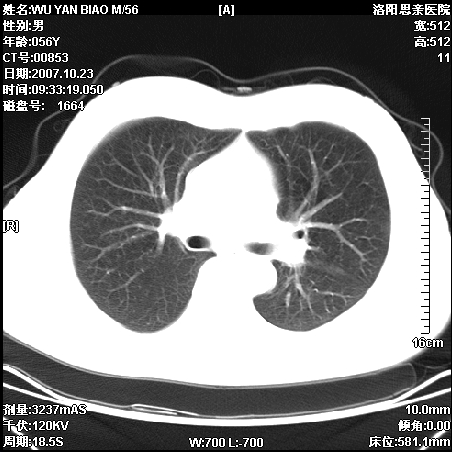

标题: CT10160:M56Y,体检发现,病人无不适,病人随访中 [打印本页]

标题: CT10160:M56Y,体检发现,病人无不适,病人随访中

后上纵隔占位,与肺交界清,宽基底附着脊柱,密度均匀,局部骨质无明确改变.

考虑;神经源性肿瘤,---起源交感n链?,不除外肠源性囊肿.

1、病灶在后纵隔脊柱旁沟内,此处是神经原性肿瘤的好发部位

2、病灶边缘光滑整齐,更说明病灶来于纵隔,由于有胸膜的包裹所以才导致这么光滑的边缘

3、病灶内的密度均匀